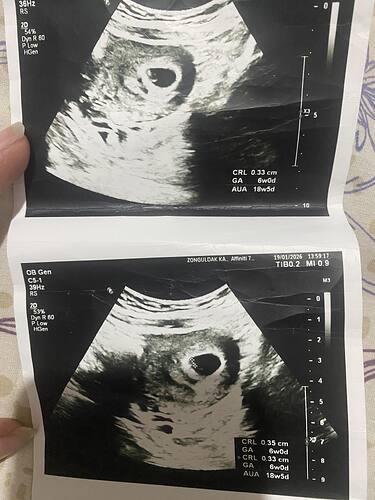

Daha çok küçük değilmi tahmin için

Evet ama bazen keseye görede tahmin yapabiliyorlar ya merak benimki

Kese yuvarlak bence kız erkek olsaydı fasulye gibi şekilli olurdu benim oglumda doktor 6 haftalıkken senin olgun olur fasulyen var demişti buda Kısmet aetık

Hayır canım fark etmemiştim seninkini ama kese şekline bakılırsa erkeğe benziyor seninki benim bebişin de kese benzerdi erkek bebek bekliyoruz![]()